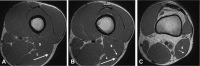

Background: Injury to the distal musculotendinous T junction (DMTJ) of the biceps femoris is a distinct clinical entity that behaves differently from other hamstring injuries due to its complex, multicomponent anatomy and dual innervation. Injury in this region demonstrates a particularly high rate of recurrence, even with prolonged rehabilitation times.

Methods: Acute injury to the DMTJ of the biceps femoris was identified in 106 MRI examinations from 55 patients at a single institution. Each injury was classified as involving the long head, the short head, or both components of the DMTJ, with each component individually graded. Injuries were classified as recurrent if there was a previous MRI demonstrating an acute injury to the DMTJ or if there was scarring present at the site of an acute injury.

Results: Of the 106 acute injuries to the DMTJ of the biceps femoris, isolated injury to the long head component was the most common (51%), with both components involved in [round 42.5% to 43%] of cases. Isolated injury to the short head component accounted for 7% of cases. The recurrence rate for reinjury to the DMTJ was 54% in this series. The date of prior injury was known in 45 of 57 recurrent cases, with 34 of these reoccurring within 3 months (76%) and 40 reoccurring within 12 months (89%). The recurrent injury was of a higher grade than the prior injury in 22 of 44 instances (50%), the same grade in 16 instances (36%), and a lower grade in 6 instances (14%). Thus, 86% of recurrent injuries were of the same or higher grade than prior injury.